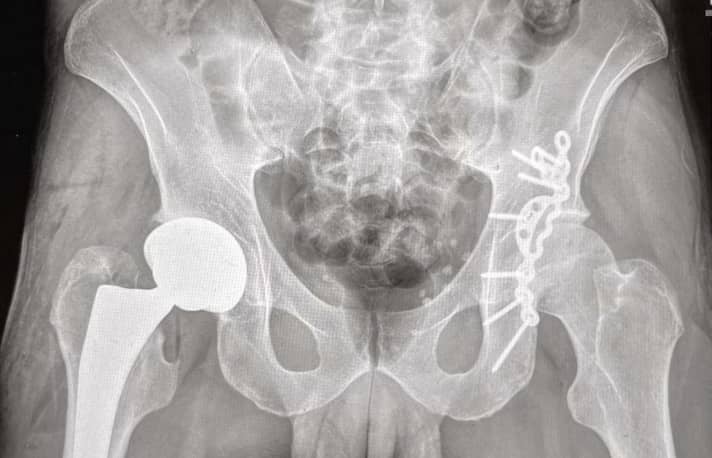

Stefan Garlicki: Steif. Doch mittlerweile geht es ganz gut, dank viel Arbeit im Gym. Die Odyssee begann 2018 bei einem Rennen in Ilmenau. Hier brach die eine Hüfte. Ich musste fast sechs Monate an Krücken gehen. Nur elf Monaten nach Ilmenau stürzte ich beim Worldcup in Leogang – hier brach die andere Hüfte. Es folgten etliche Operationen. Auf der einen Seite hab’ ich seit letztem September ein künstliches Gelenk. Ich glaube, ich bin der einzige Downhill-Worldcupper mit einer Hüftprothese.